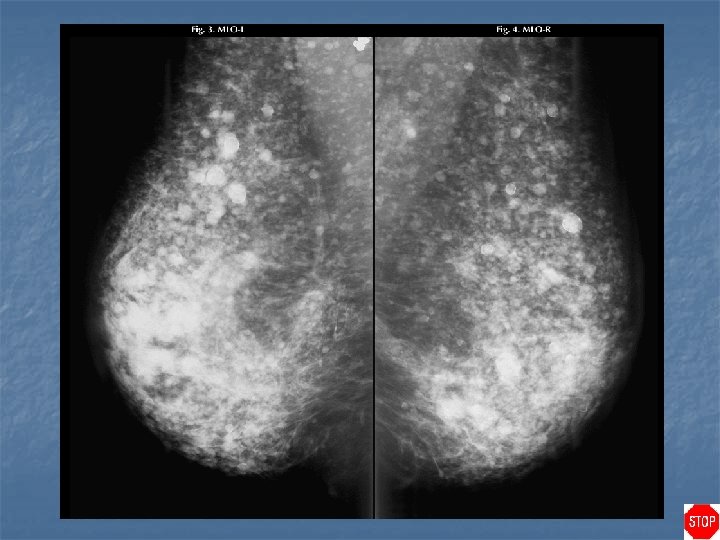

Silicone injection n Innumerable high density rim-calcified masses are seen, characteristic of silicone granulomas